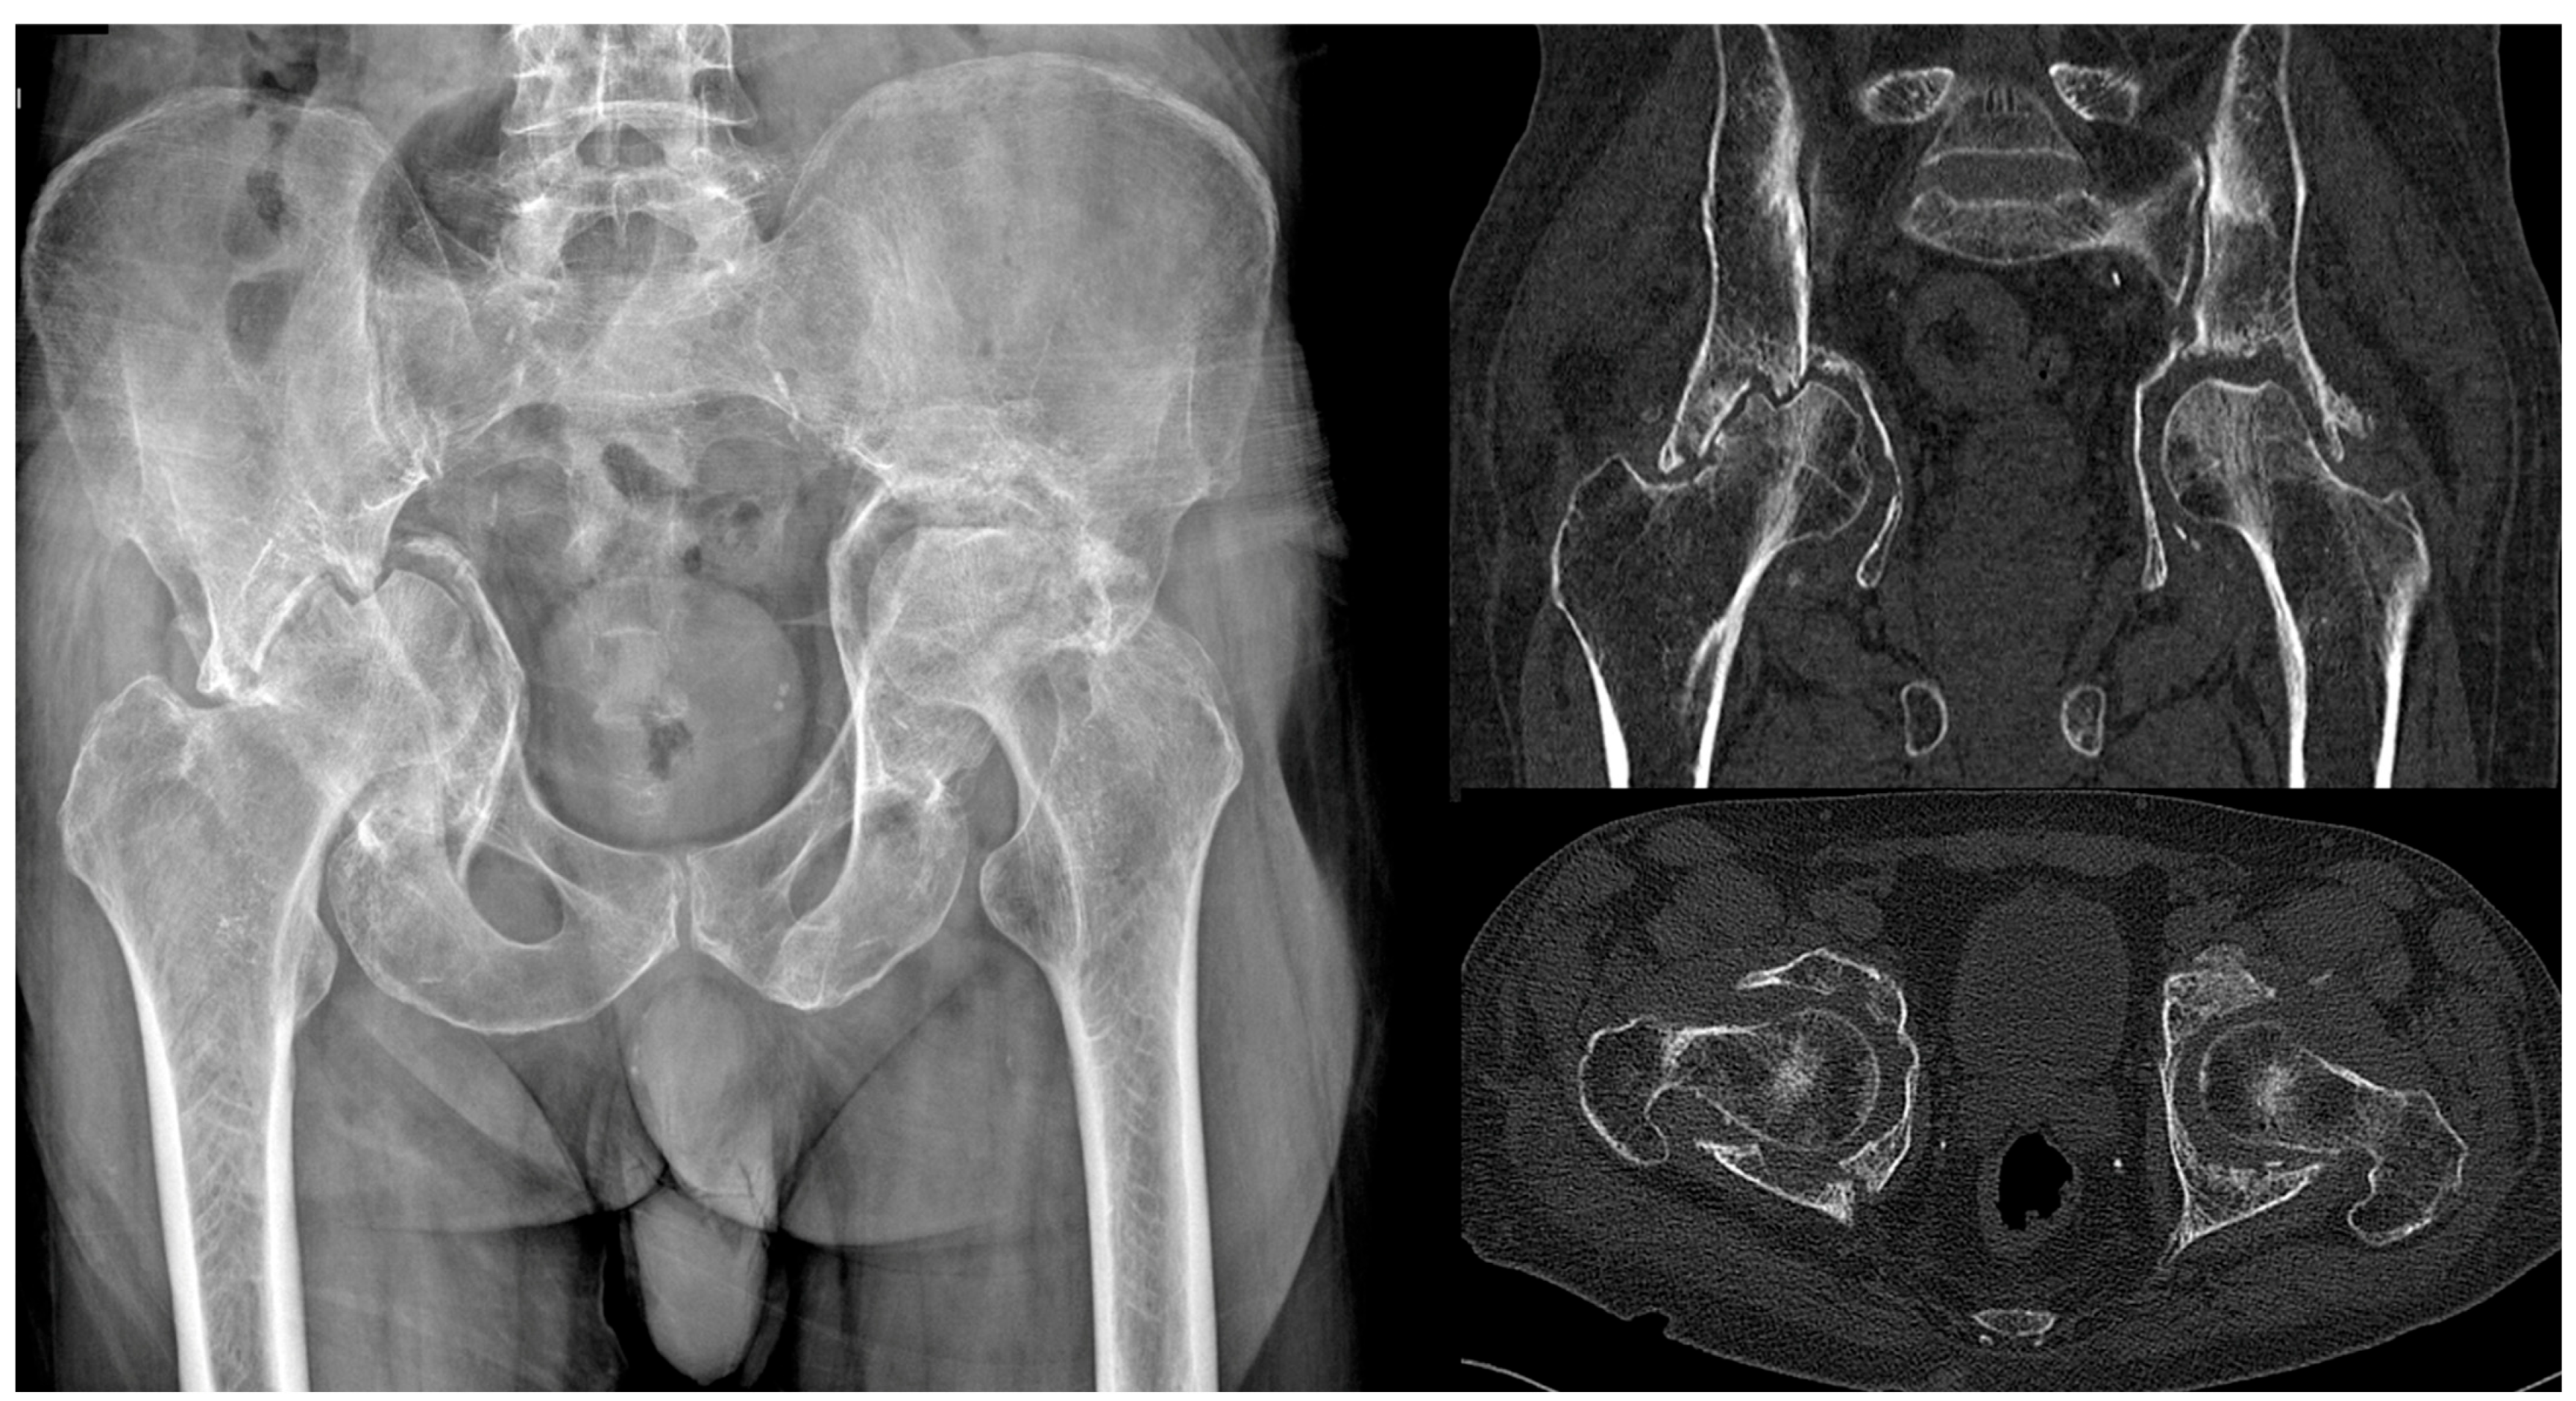

4.1. Delayed THA, Neglected, or Conservatively Treated Acetabular Fractures

Acetabular Exposure, Preparation, and Cup Fixation